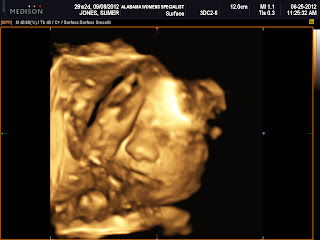

Annie Morgan Jones

We had our 4 D ultrasound yesterday and finally got to see her sweet little face.

We did not think she was going to let us see her whole face at one time because for the first 15 minutes she had one arm and both of feet in front of her face...She made us work for it :)

I think something about her looks like Ellie but she looks different to me too. Her face is much fuller than Ellie's 4D picture and their nose looks different too But I think she is just so sweet looking. Her cheeks are already so big... I cannot wait to kiss on them.